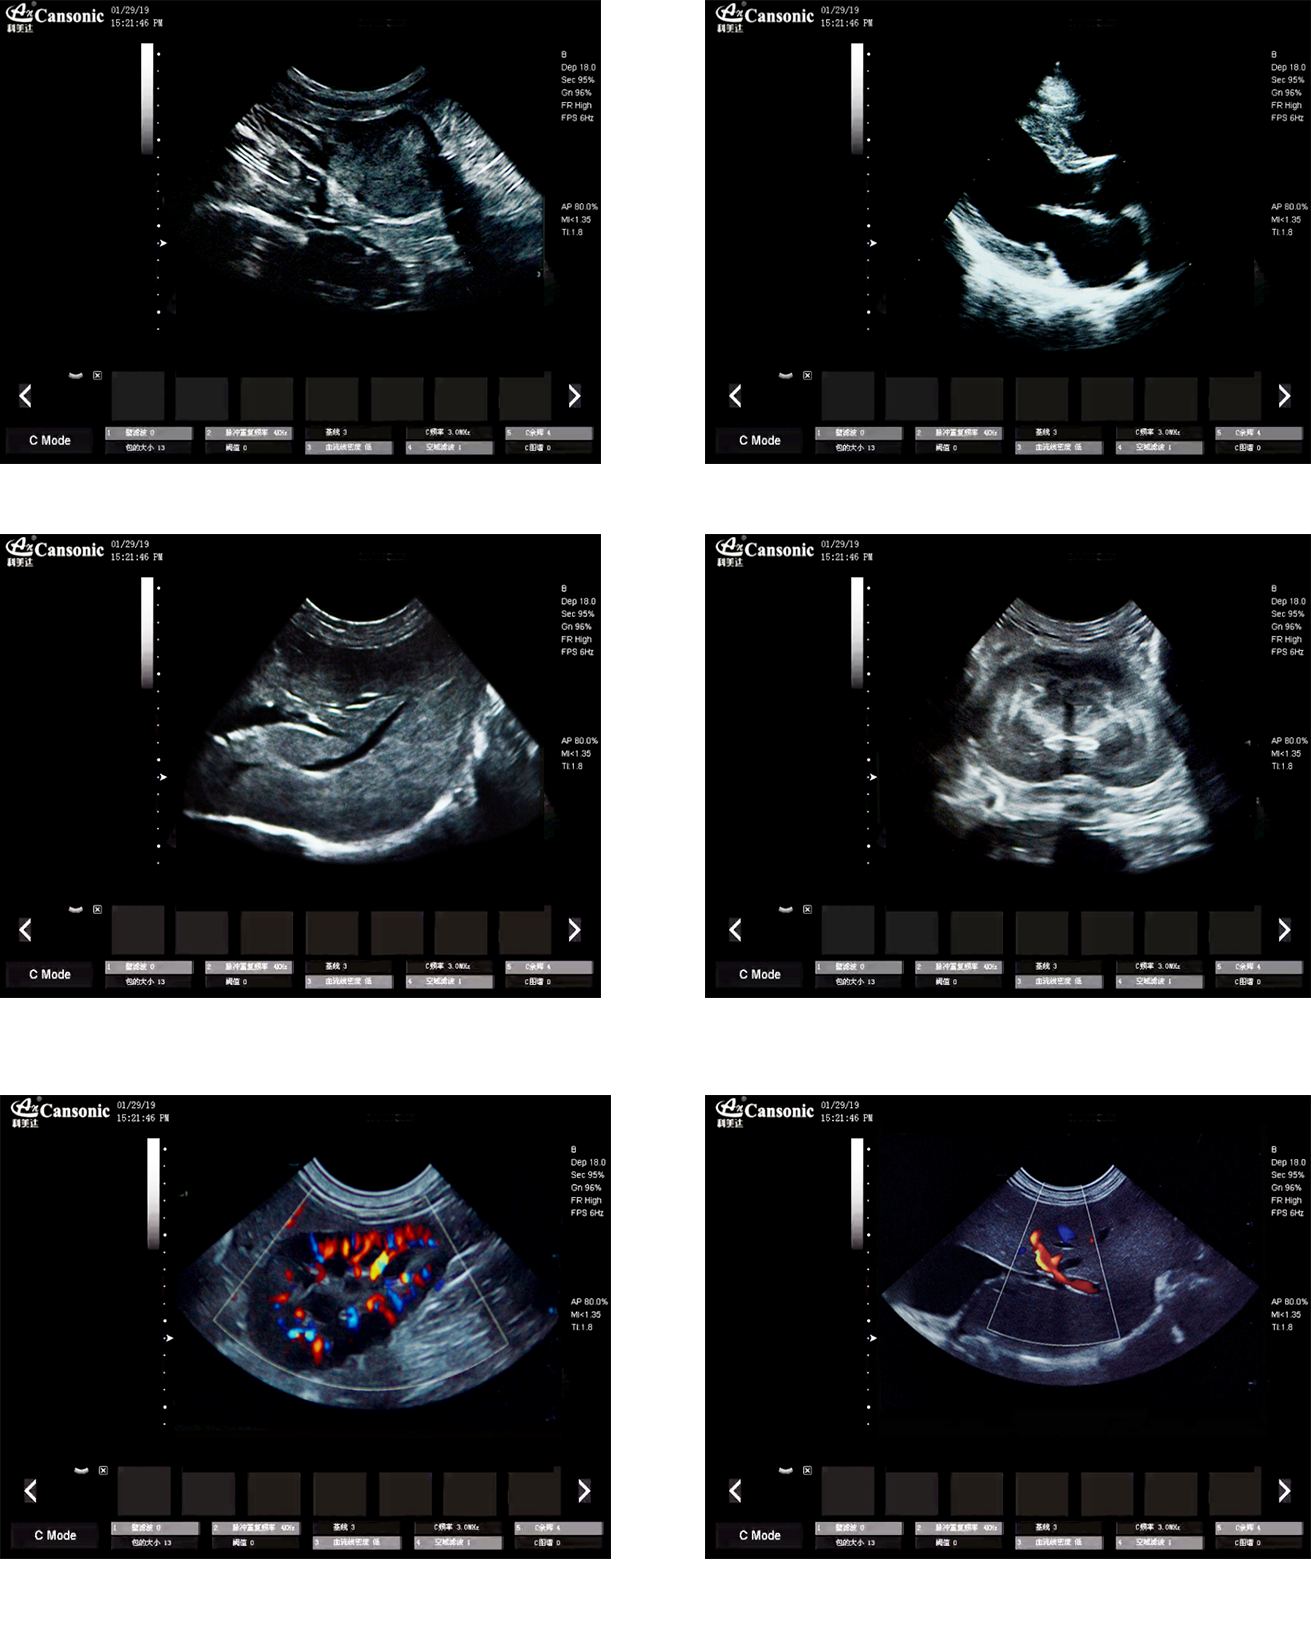

1、薈萃高端彩超的專業技術,各類型的專業獸用探頭,提供完整的動物臨床診療方案

2、專業的獸用彩超軟件,適合犬、貓、馬、牛、羊等各類大小動物彩超檢查

3、完備的獸用高端功能,能量多普勒POWER模式彩色多普勒Color成像模式

4、精準全數字濾波技術,有效降低多普勒噪聲及運動偽像,提升多普勒超聲圖像

臨床圖示